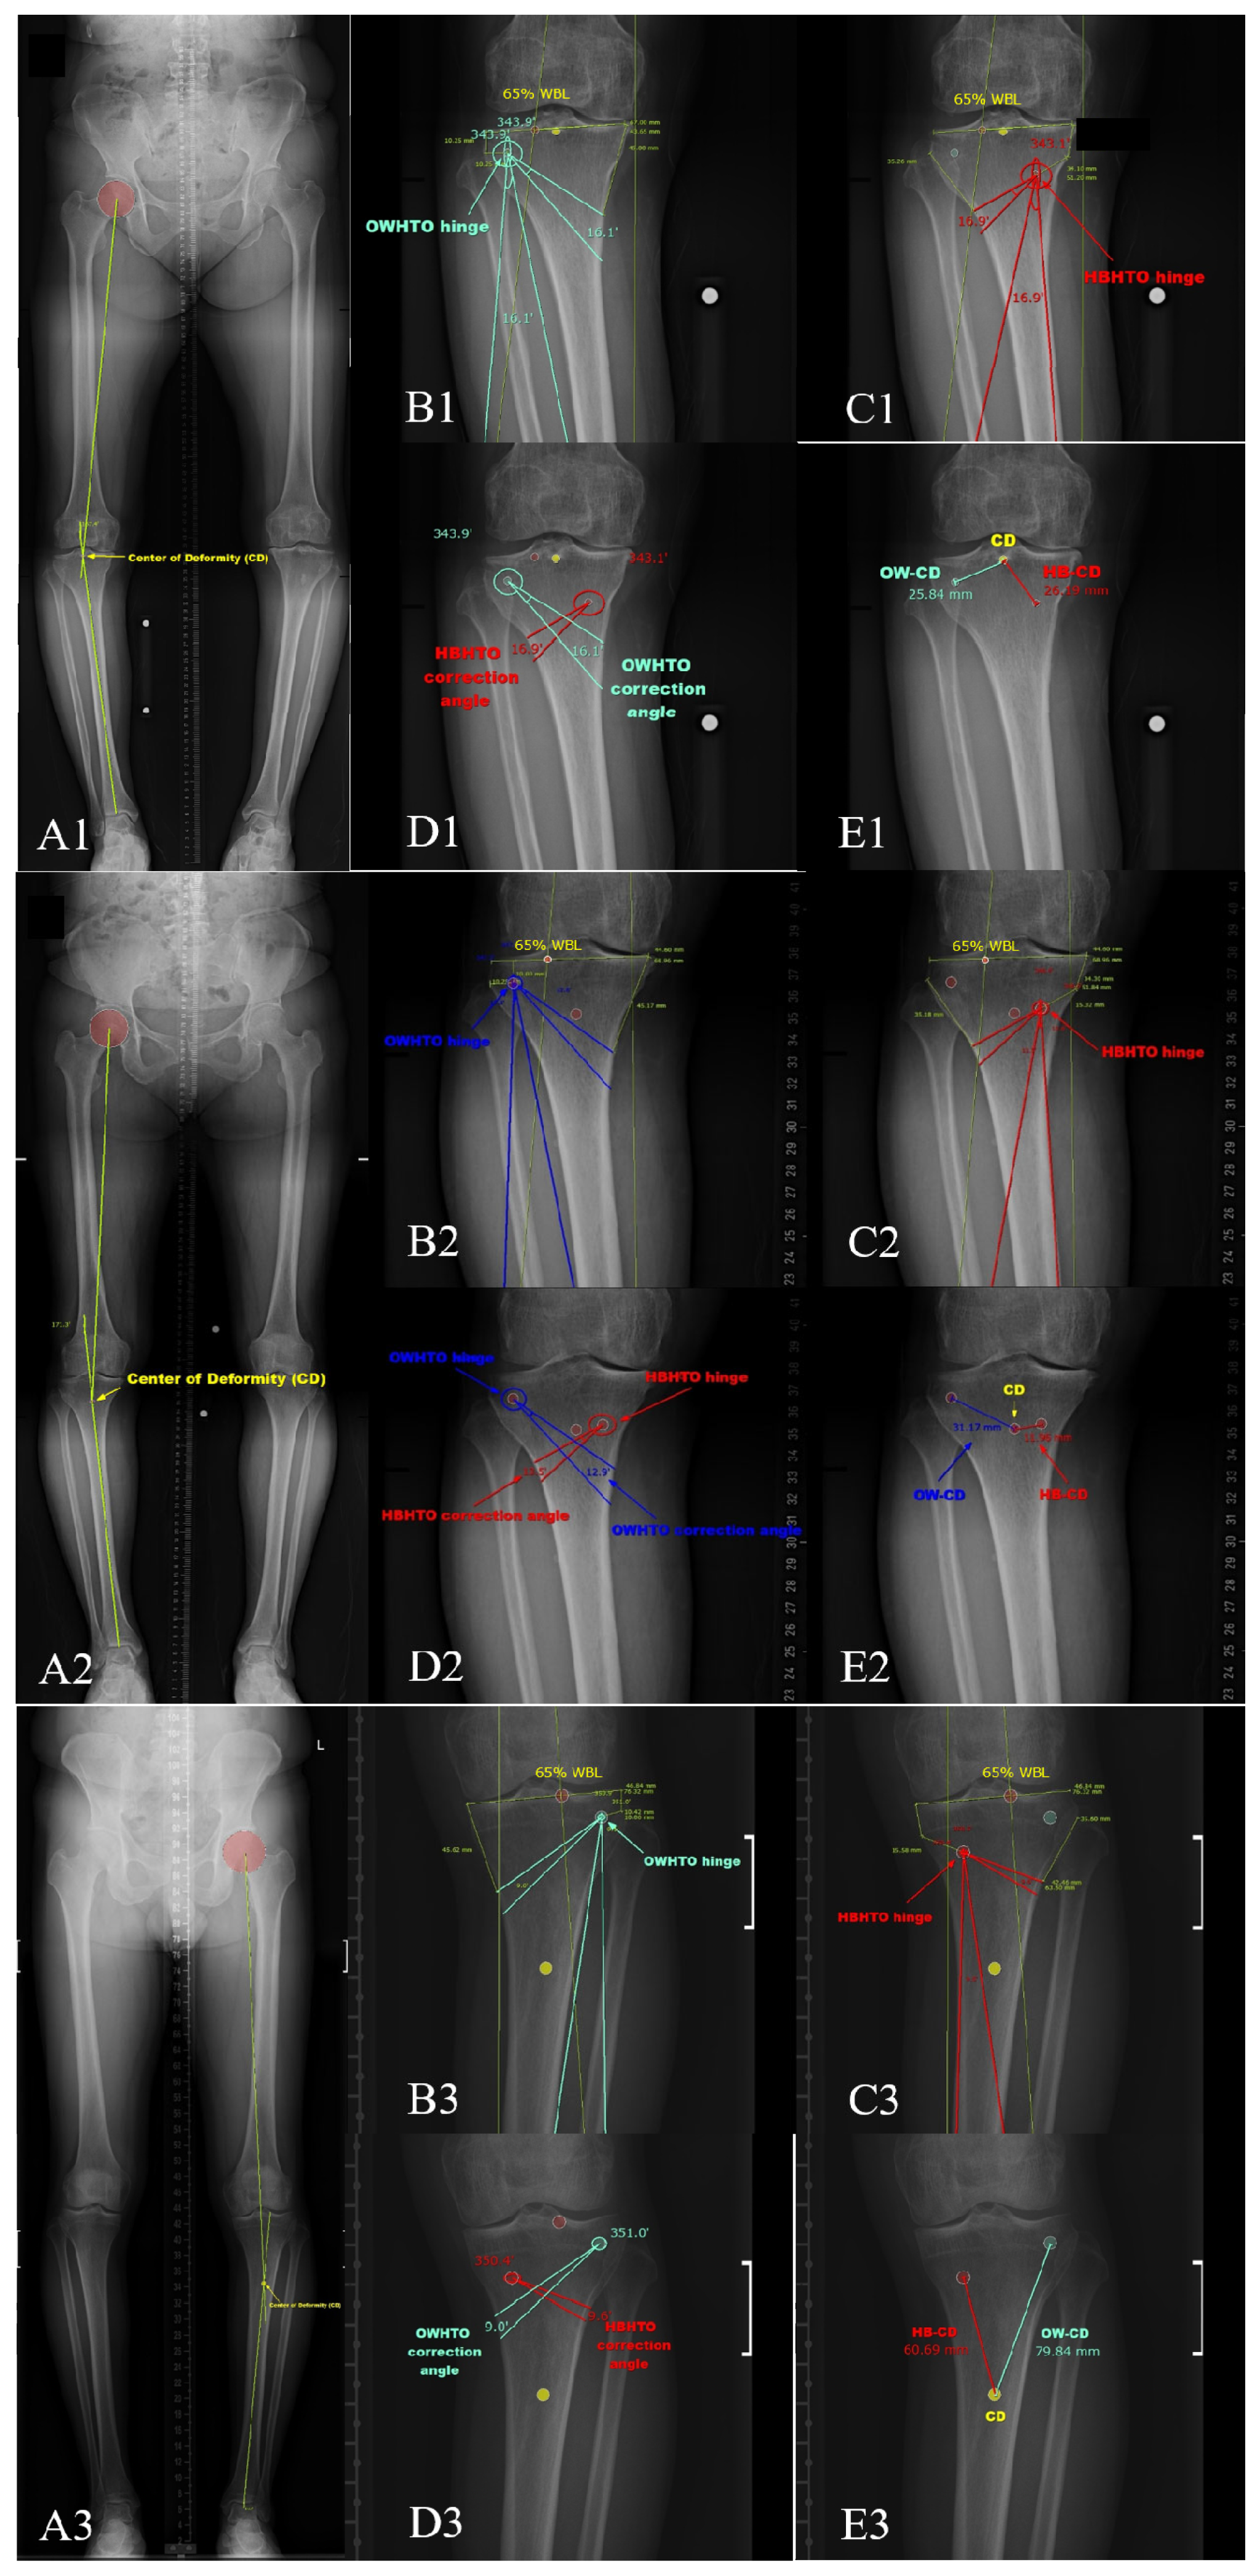

| 65% WBL Target | HBHTO Plan | OWHTO Plan | p-Value |

|---|---|---|---|

| Correction angle (°) | 14.86 ± 3.47 (8.3~24) | 14.09 ± 3.29 (7.9~22.9) | <0.001 * |

| CAD (°) | 0.78 ± 0.22 (0.4~1.5) | ||

| HB/OW angle ratio | 1.06 ± 0.01 (1.03~1.08) | ||

| WBL change (%) per correction angle | 3.9 ± 0.3 (3.0~4.6) | 4.1 ± 0.3 (3.1~4.7) | <0.001 * |

| Hinge–CD distance (mm) | 31.60 ± 18.41 (12.6~99.1) | 47.96 ± 20.56 (20.4~118.8) | <0.001 * |

| dHCD (mm) | 16.35 ± 4.74 (−2.68~23.91) | ||

| HBCD/OWCD ratio | 0.63 ± 0.13 (0.39~1.11) | ||

| High-CD Position (N = 42) | Low-CD Position (N = 54) | p-Value | |

| HKA (°) | 11.33 ± 3.07 (5.1~17.6) | 8.60 ± 2.97 (3.7~15.1) | <0.001 * |

| mLDFA (°) | 89.41 ± 1.55 (86.6~93.2) | 88.72 ± 2.67 (83.7~97.9) | 0.139 |

| JLCA (°) | 5.65 ± 2.81 (1.8~12.6) | 3.63 ± 2.67 (−3.4~9.9) | 0.001 * |

| MPTA (°) | 83.09 ± 2.02 (75.9~88.4) | 82.05 ± 2.07 (75.8~85) | 0.016 * |

| Leg length (mm) | 707.30 ± 46.34 (633.2~838.17) | 722.23 ± 45.20 (611.1~818.82) | 0.117 |

| Length, tibia (mm) | 307.63 ± 21.39 (272.1~378.2) | 311.91 ± 36.08 (103.8~362.7) | 0.471 |

| Width, proximal tibia (mm) | 72.47 ± 4.64 (64.58~84.84) | 73.26 ± 5.63 (64.59~86.38) | 0.457 |

| Preop. WBL position (%) | 1.9 ± 13.3 (−29.4~30.3) | 12.6 ± 11.5 (14.1~31.2) | <0.001 * |

| WBL change (%) | 63.1 ± 13.3 (34.7~94.4) | 52.4 ± 11.5 (33.8~79.1) | <0.001 * |

| Correction in OWHTO (°) | 15.73 ± 3.11 (8.9~22.9) | 12.61 ± 2.80 (7.9~18.8) | <0.001 * |

| Correction in HBHTO (°) | 16.58 ± 3.27 (9.6~24) | 13.32 ± 2.97 (8.3~19.9) | <0.001 * |

| CAD (°) | 0.86 ± 0.21 (0.5~1.5) | 0.70 ± 0.20 (0.4~1.2) | <0.001 * |

| OWCD (mm) | 33.17 ± 6.02 (24.87~49.88) | 61.20 ± 19.15 (37.55~118.8) | <0.001 * |

| HBCD (mm) | 17.67 ± 3.65 (12.6~26.87) | 43.013 ± 18.18 (20.83~99.1) | <0.001 * |

| dHCD (mm) | 15.51 ± 4.01 (7.67~23.91) | 18.19 ± 2.43 (12.09~22.45) | <0.001 * |